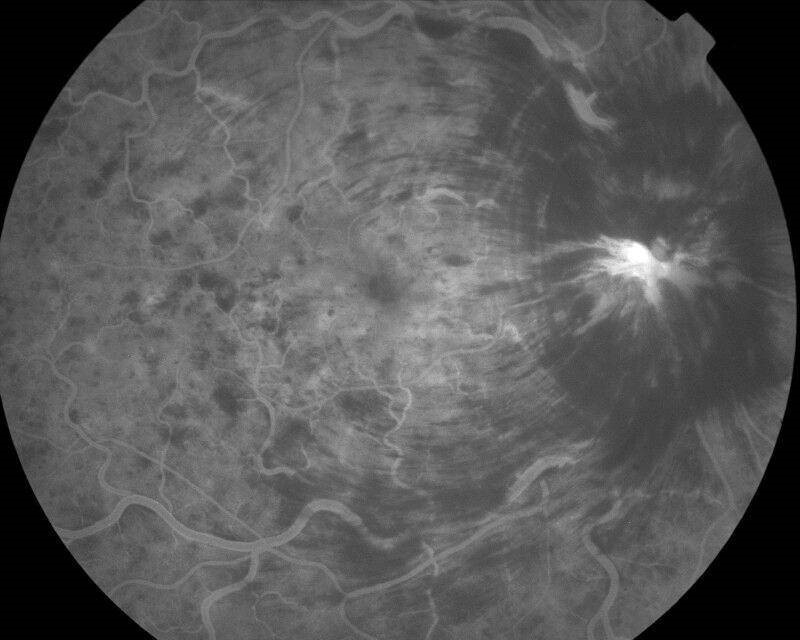

Une patiente de 75 ans arrive aux urgences ophtalmologiques pour sensation de baisse d’acuité visuelle brutale de l’œil droit depuis le matin au réveil.

Elle décrit également une ondulation des lignes à la lecture.

Son œil droit est blanc et indolore. On retrouve une acuité visuelle chiffrée à moins de 0,5/10e à droite contre 8/10e à gauche. Il n’y a pas de notion de traumatisme.

L’examen du RPM est important car il peut orienter vers un diagnostic grave (OACR/NOIAA), mais c’est l’imagerie et la biologie qui motiveront la mise en place du traitement en urgence.